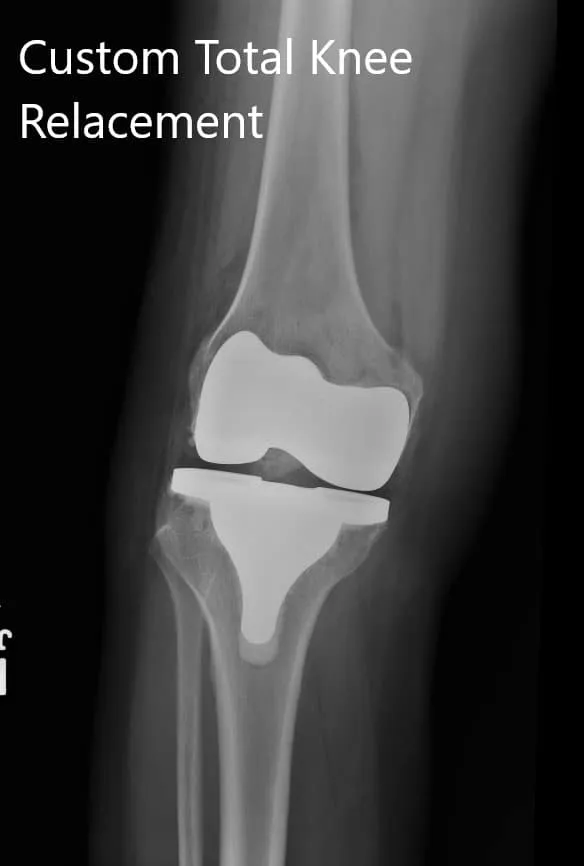

Imágenes postoperatorias que muestran vistas AP y oblicuas de la rodilla derecha.